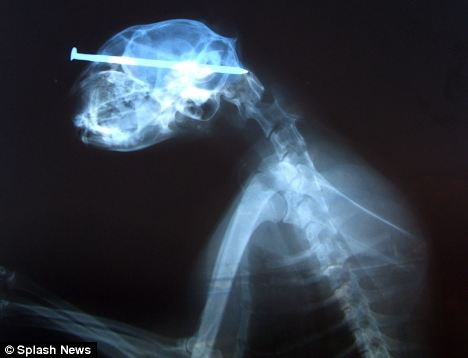

當(dāng)時(shí)照的X光圖

雖然人人都說貓有9條命,但是看到小貓“奇異恩典”頭插8厘米鐵釘在街頭漫步時(shí)你一定還會(huì)驚嘆,貓的生命力真是太強(qiáng)大了!

據(jù)英國媒體5月25日?qǐng)?bào)道,“奇異恩典”生活在美國艾奧瓦州西部港口城市蘇城,盡管頭部被一個(gè)惡棍插進(jìn)去了8厘米長(zhǎng)的鐵釘,但它卻什么事兒也沒有,還好端端地在街頭閑逛。

最終,有人發(fā)現(xiàn)了小貓頭部的異物,并將它送到了獸醫(yī)那兒。經(jīng)過手術(shù),獸醫(yī)將它頭上的鐵釘成功拔出。為小貓主刀的辛迪?拉萊特醫(yī)生稱:“我從來沒見過這樣的事,受這么重的傷居然還能和沒事一樣,太神奇了。”